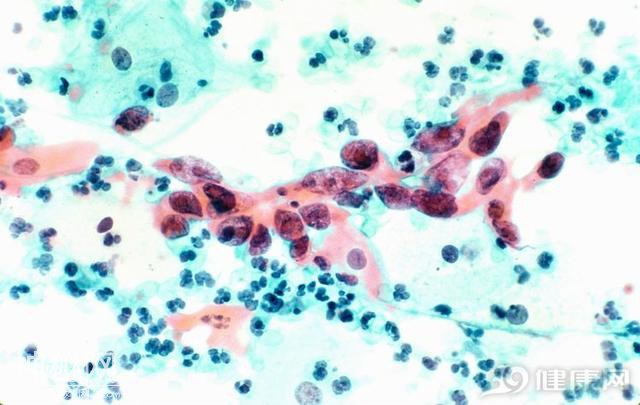

确实,很多癌症的死亡率是很高的,虽然癌细胞增长的速度很快,但是从普通疾病到肿瘤,再到恶化成癌症,直至死亡,这是需要时间的,及时发现才是关键。而且癌症分为很多种,有些癌症合理治疗,病人的寿命和普通人也没什么区别。

出现癌症并不代表自己即将和死神见面,若是出现黑色素瘤,甲状腺癌,霍奇金淋巴瘤以及宫颈癌,乳腺癌和睾丸癌,这些癌症及时发现,五年内的的生存率还是非常高的。其中以下这三种癌症的治愈率就比较高,患者不用太灰心。